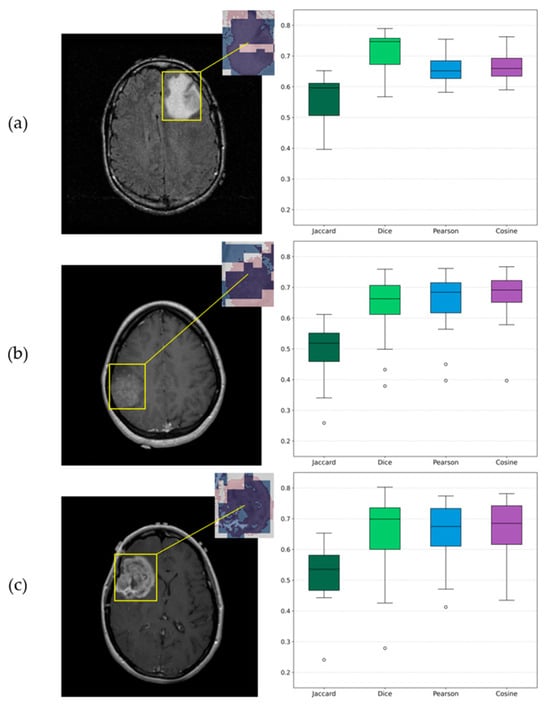

Deep learning models for three-dimensional (3D) data are increasingly used in domains such as medical imaging, object recognition, and robotics. At the same time, the use of AI in these domains is increasing, while, due to their black-box nature, the need for explainability has grown significantly. However, the lack of standardized and quantitative benchmarks for explainable artificial intelligence (XAI) in 3D data limits the reliable comparison of explanation quality. In this paper, we present a unified benchmarking framework to evaluate both intrinsic and post hoc XAI methods across three representative 3D datasets: volumetric CT scans (MosMed), voxelized CAD models (ModelNet40), and real-world point clouds (ScanObjectNN). The evaluated methods include Grad-CAM, Integrated Gradients, Saliency, Occlusion, and the intrinsic ResAttNet-3D model. We quantitatively assess explanations using the Correctness (AOPC), Completeness (AUPC), and Compactness metrics, consistently applied across all datasets. Our results show that explanation quality significantly varies across methods and domains, demonstrating that Grad-CAM and intrinsic attention performed best on medical CT scans, while gradient-based methods excelled on voxelized and point-based data. Statistical tests (Kruskal–Wallis and Mann–Whitney U) confirmed significant performance differences between methods. No single approach achieved superior results across all domains, highlighting the importance of multi-metric evaluation. This work provides a reproducible framework for standardized assessment of 3D explainability and comparative insights to guide future XAI method selection.